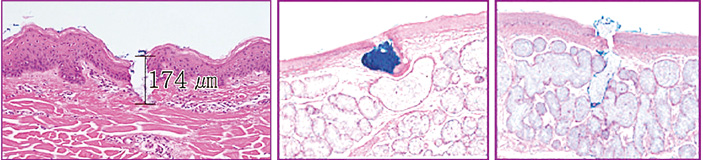

再生因子が最も効果を発揮するのは真皮内と言われており、オスモインジェクターはその真皮層に薬液を確実に届けるための注入機器です。

※オスモインジェクター使用時の皮膚の組織像

その最大の特徴は、針のスパイラル構造であり、40Gというきわめて細い針でもしっかりと薬液を真皮内に届けることができます。